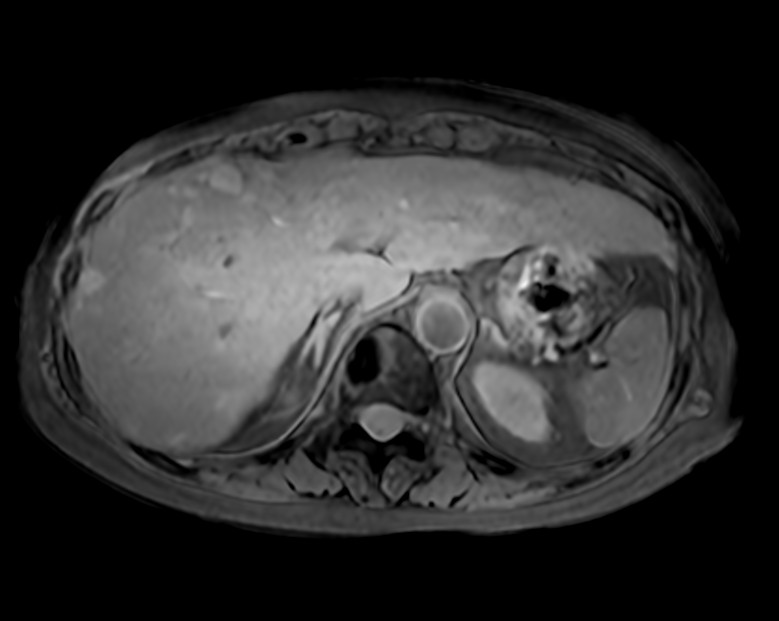

Axial eTHRIVE 3 min Post gado